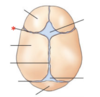

1

Q

Give the Aspect

A

Anterior View

2

Q

A

Humerus

3

Q

A

Arm

4

Q

A

Metacarpals

5

Q

A

Elbow Joint

6

Q

A

Acromion

7

Q

A

Shoulder